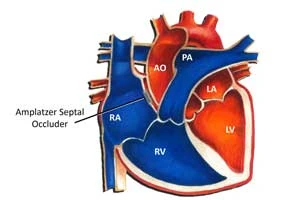

ASD Closure (Atrial Septal Defect)

Closure of hole between heart's upper chambers

ASD Closure (Atrial Septal Defect)

Closure of hole between heart's upper chambers